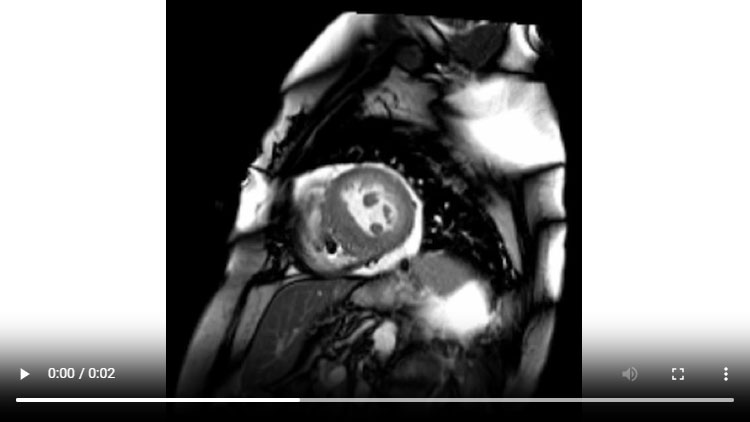

Figure 1B : Séquence Ciné-IRM - Coupes petit-axe médian

- Présence d’une hypertrophie ventriculaire gauche (HVG) asymétrique à prédominance septale mesurée au maximum à 23 mm.

- Visualisation de la sonde de PM avec artéfacts métalliques modérés au niveau du ventricule droit (flèches roses).

- Présence d’un épanchement péricardique de moyenne abondance (flèches rouges).